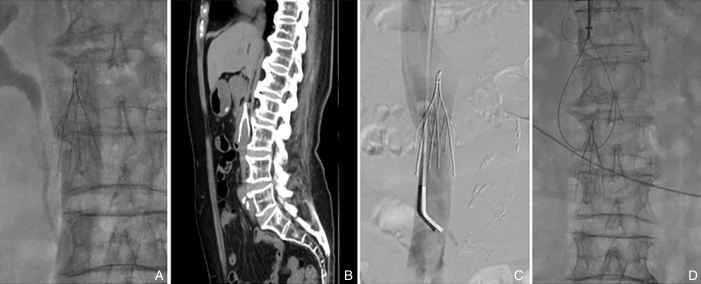

图2 Octoparms滤器的置入与取出 A:滤器的置入,位置、形态良好;B:滤器回收贴壁;C:滤器贴壁、头端移位至左肾静脉开口;D:常规圈套失败后LOOP技术取出Fig.2 Insertion and retrieval of the Octoparms filter A: Filter insertion with proper positioning and morphology; B: Filter retrieval with adhesion to the vessel wall; C: Filter adhesion and displacement of the head to the opening of the left renal vein; D: Retrieval using the LOOP technique after routine snare failure